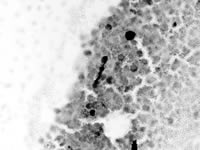

切除した肺からは、アスベスト小体(写真4=鉄アレイの形に見えるのがアスベスト繊維。肺に入った後に固まったものです)が見つかり、現在労災を申請中 です。最近このような患者や家族の方からの問い合わせが多くなっています。